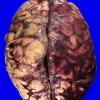

Hemorrhage, hypertensive (5)